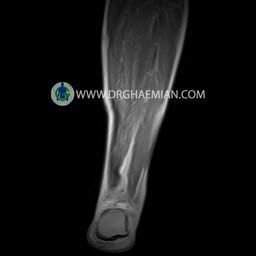

پزشکان اغلب از تصویربرداری ام آر آی برای تشخیص و درمان عارضه های پزشکی که فقط با استفاده از اشعه ایکس یا میدان مغناطیسی و امواج رادیویی قابل مشاهده است، استفاده می کنند. دستگاه ام آر آی تصاویر دقیق از ساختار های داخلی بدن ایجاد می کند. در این کیس پارگی تاندون آشیل با 12 mm فاصله مشاهده می شود.

LEFT CALF MRI

(FOR EVALUATION OF ACHILLES TENDON )

( without contrast )

Technique : Coronal , sagittal T1 and T2 , Axial T2 fatsat .

REPORT:

The tibia and fibula show normal signal and configuration .

The cortical bone appear normal .

Surrounding muscular layers appear normal .

– Heterogeneous signal change in distal of achilles tendon suggestive for complete tearing with (12 mm gap ) & adjacent soft tissue swelling

is seen